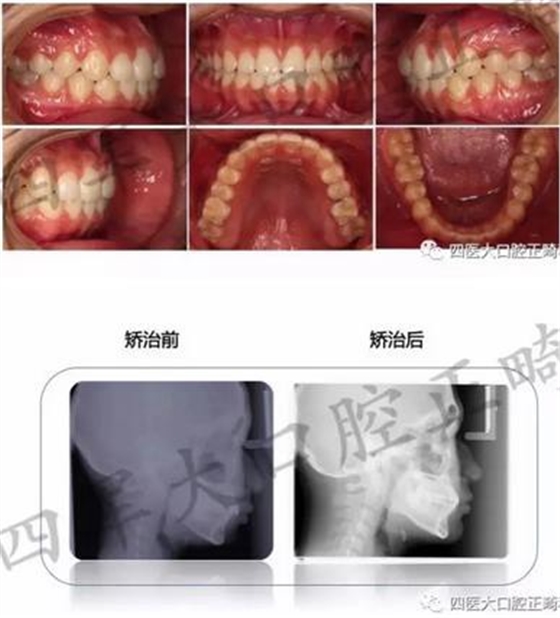

這樣呢?